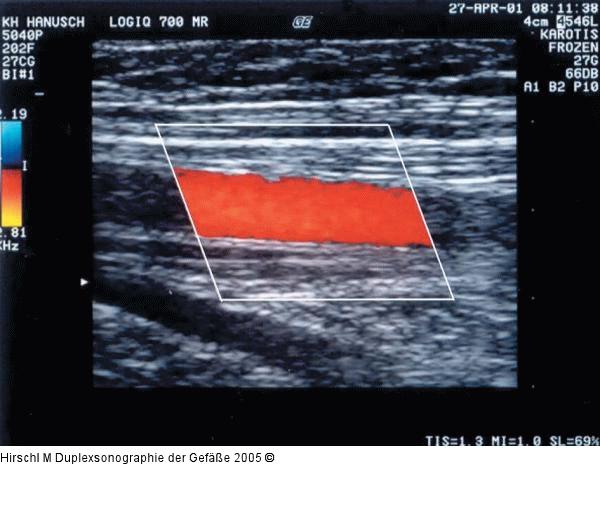

Abbildung 7: Duplexsonographie - Farbgain Richtig eingestelltes Farbgain am Beispiel einer ACC in Halsmitte: in der Bildmitte hellrote bis gelbe Farbschattierungen als Ausdruck der maximalen Strömungsgeschwindigkeit, am Gefäßrand dunkelrote Farbkodierung (laminare Strömung in einer Strömungsrichtung). |

Abbildung 7: Duplexsonographie - Farbgain

Richtig eingestelltes Farbgain am Beispiel einer ACC in Halsmitte: in der Bildmitte hellrote bis gelbe Farbschattierungen als Ausdruck der maximalen Strömungsgeschwindigkeit, am Gefäßrand dunkelrote Farbkodierung (laminare Strömung in einer Strömungsrichtung). |